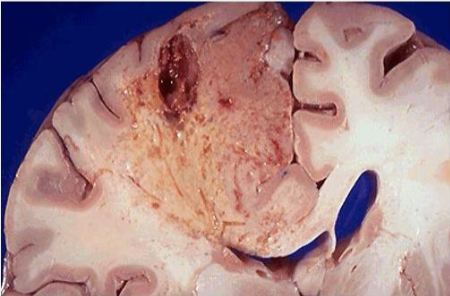

term image

White anemic infarct

Myocardial infarct